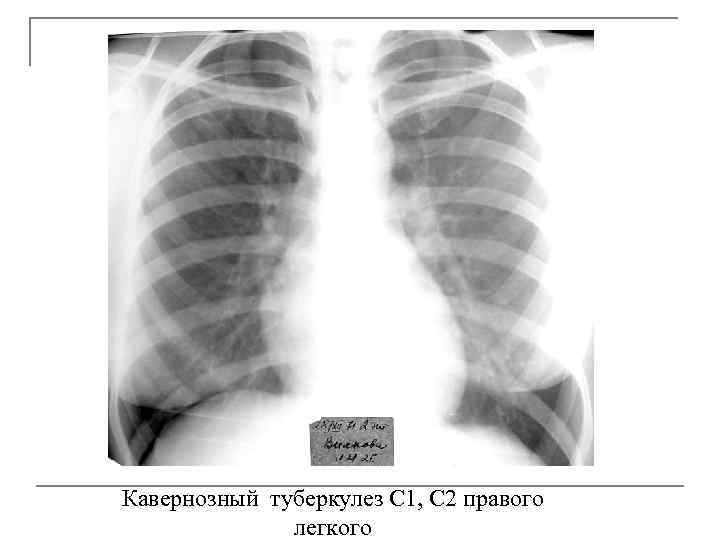

Кавернозный туберкулез q q Характеризуется наличием сформированной каверны с отсутствием выраженных фиброзных изменений в окружающей каверну легочной ткани. Развивается кавернозный туберкулез у больных инфильтративным, диссеминированным, очаговым туберкулезом, при распаде туберкулем; при позднем выявлении заболевания, когда фаза распада завершается формированием каверн, а признаки исходной формы исчезают.

Рентген - признаки q расположены в задних сегментах верхних долей рядом с главной междолевой щелью, q имеют ровные гладкие стенки толщиной 1 -2 мм, жидкость в полости отсутствует, q в окружающей легочной ткани выявляют мелкие очаги, участки эмфиземы, тонкие линейные тяжи к плевре. q просвет дренирующего бронха может быть хорошо виден, если он расположен параллельно плоскости сканирования, стенки его обычно утолщены, просвет несколько расширен.

Кавернозный туберкулез С 1, С 2 правого легкого